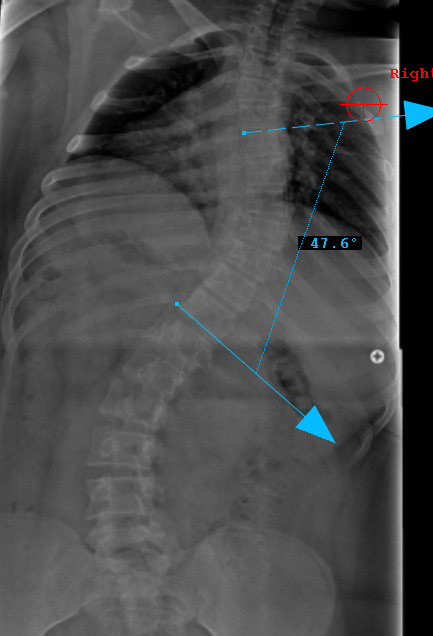

Preop PA View

Preop LAT View